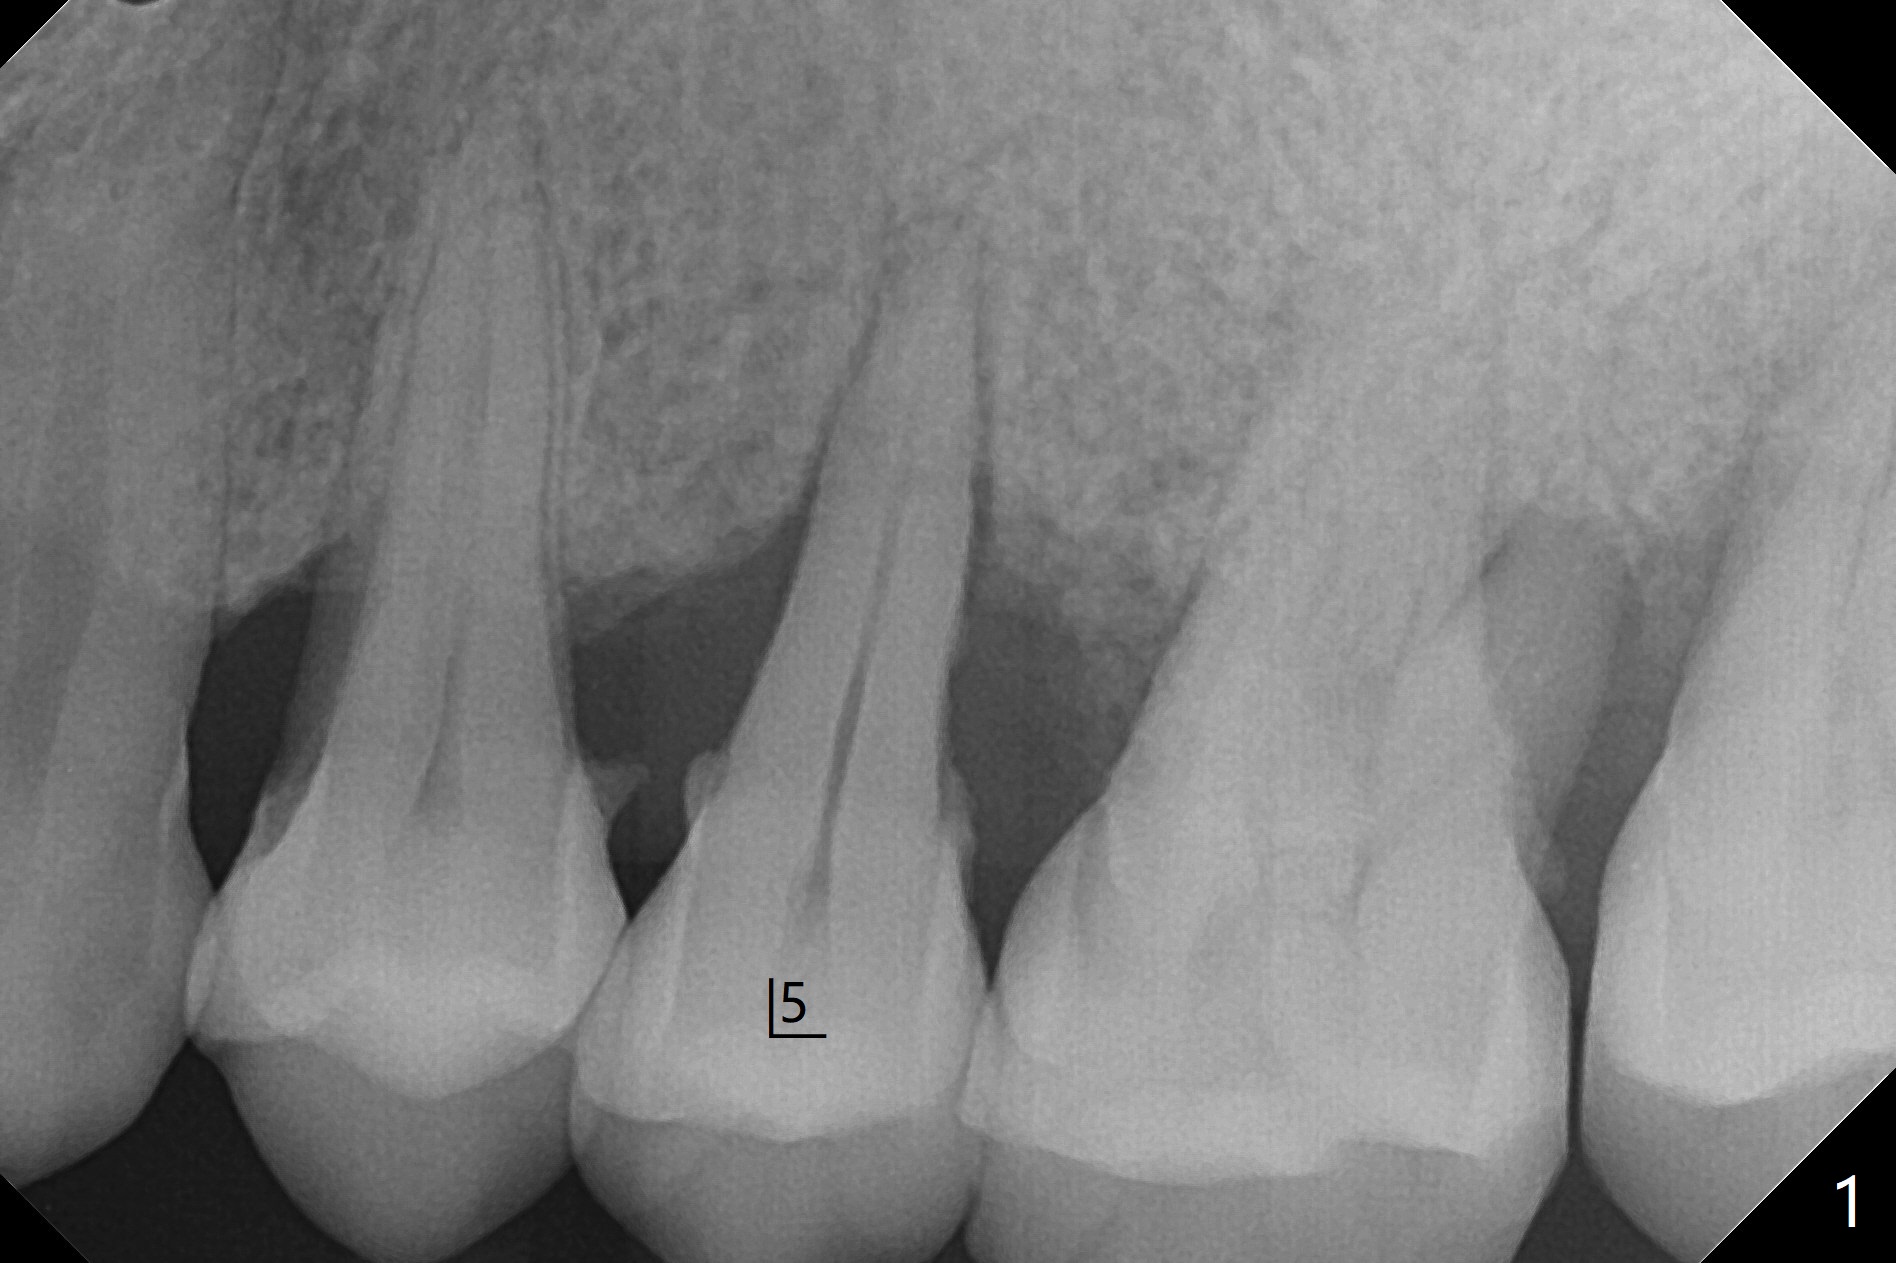

48岁女,严重牙周炎,要求拔除左上5松动牙(图一),经过劝说同意位点保留(图二)。在软组织(厚)区的骨粉(*, cortical, pressed collagen plug, perio dressing)以后帮助植牙?没毛病,不久就会吸收了,多可少,少不可多,大可小,小不可大。Steven